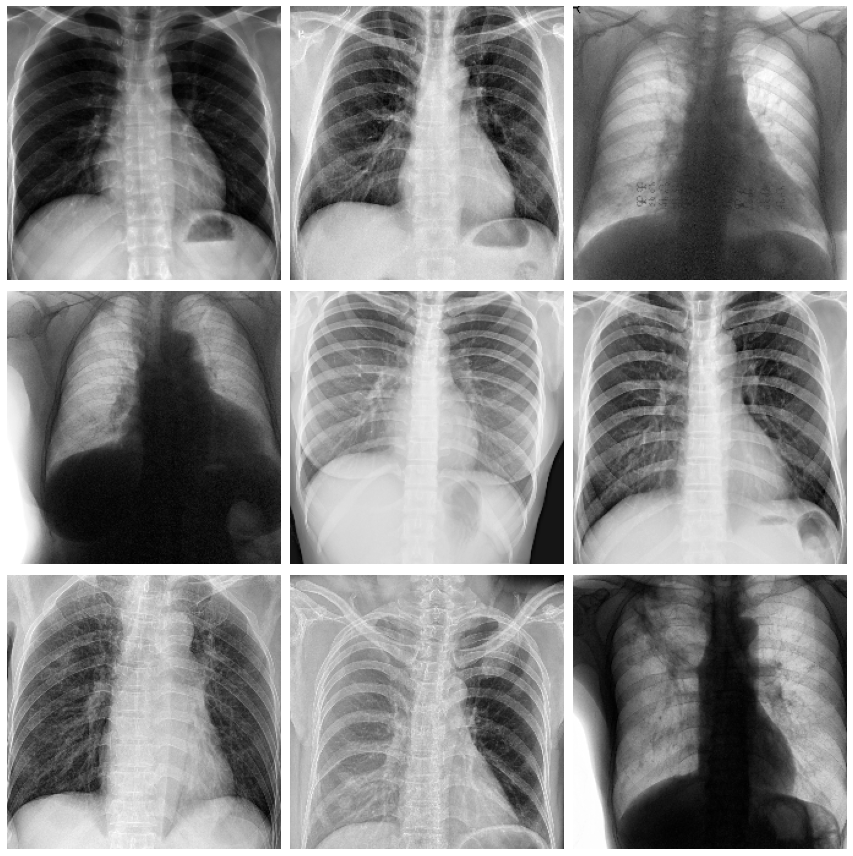

After joining the competition and reading the description, looking at data, and understanding the evaluation, you can fire up your favorite python editor and start importing packages. Though this competition has a dataset composed of dicom images that are over 128 gb in size, some nice person wrote a script and saved the dataset to a more palatable 50gb of png images. Now on to looking at the data. The data is comprised of a csv file with the image id and classification data, along with other bounding box metadata that we won't look at at this point.